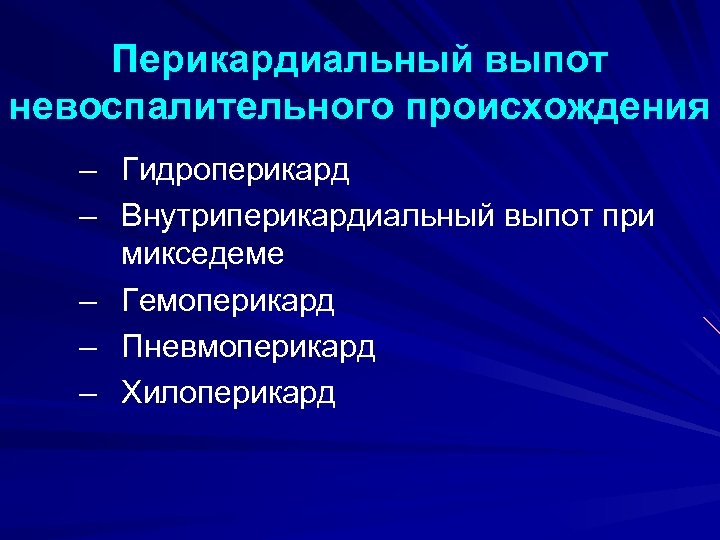

Перикардиальный выпот невоспалительного происхождения – Гидроперикард – Внутриперикардиальный выпот при микседеме – Гемоперикард – Пневмоперикард – Хилоперикард